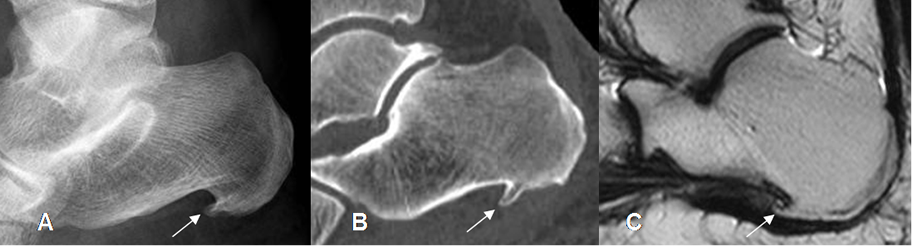

En la Rx lateral, puede identificarse un espolón calcáneo, pero debe tenerse en cuenta que puede estar presente en el 25% de pacientes asintomáticos. (1). (Fig 114).

Fig 114. Espolón calcáneo.

A: Rx lateral, B: TAC reconstrucción sagital y C: RM T2 sagital del tobillo.